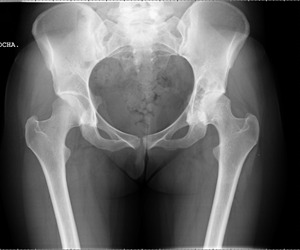

Según el enfermero, el paciente llegó con su esposa, quejándose de estreñimiento severo. Tomaron una radiografía y la examinaron.

"Pudimos ver perfectamente un objeto grande atascado en el intestino grueso", afirmó Pope en el show. "Es la primera vez que he encontrado un vibrador encendido todavía adentro de alguien".